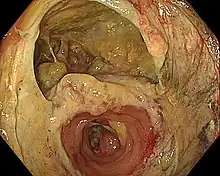

- Gastrointestinal (GI) tract: Esophagus, stomach, small bowel, large bowel, bile ducts, and pancreas. Virtually all elective resections of gastrointestinal organs are followed by anastomoses to restore continuity; pancreaticoduodenectomy is considered a massive operation, in part, because it requires three separate anastomoses (stomach, biliary tract and pancreas to small bowel). Bypass operations on the GI tract, once rarely performed, are the cornerstone of bariatric surgery. The widespread use of mechanical suturing devices (linear and circular staplers) changed the face of gastrointestinal surgery. A suture-free method for anastomosis of the colon to colon or rectum has been developed.[1][2]